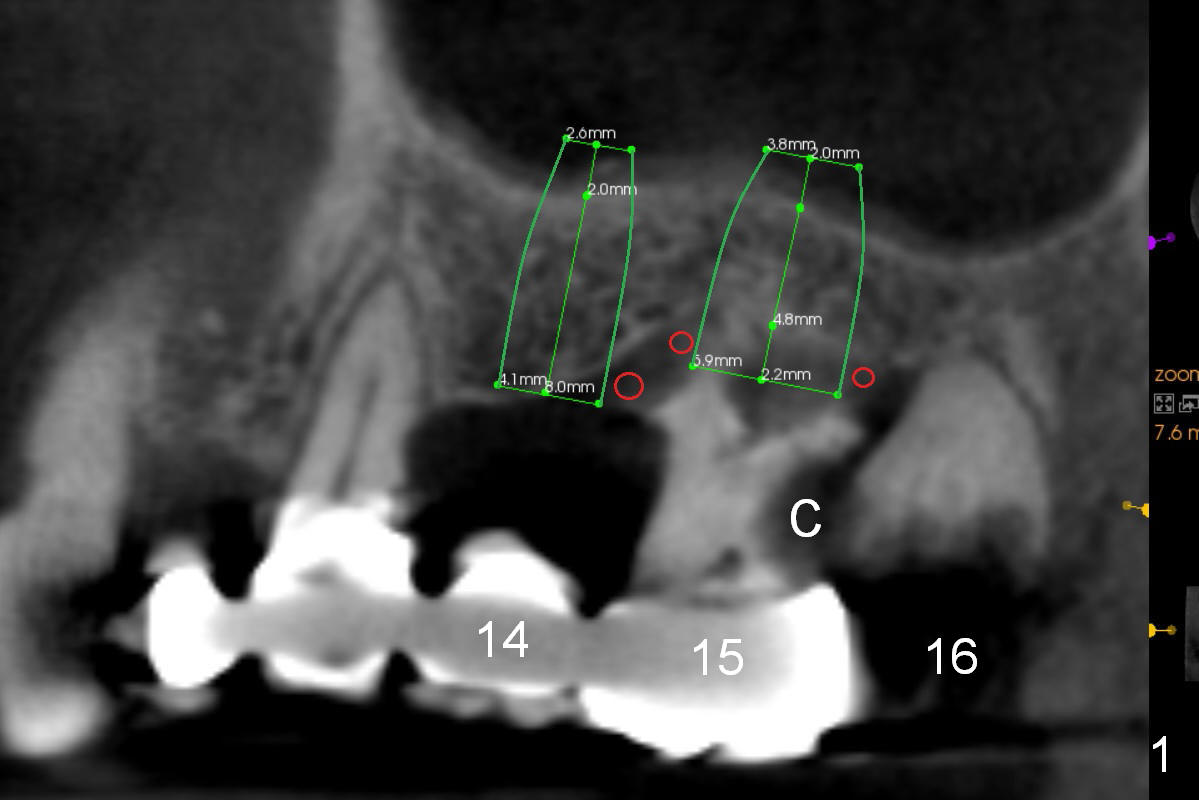

The tooth #15 of a 56-year-old man appears to be non-salvageable due to the large distal cervical caries (Fig.1 (CBCT) C). Immediately after extraction and socket debridement and antibiotic soaking, a 2 mm pilot drill is used for 4 mm, followed by 2.8 and 3.6 mm round burs for 4-6 mm (Fig.1,2 (coronal section)). At #14, the initial depth for 2 mm and 2.8 mm drills is 7 mm. The depth may increase until 9 mm (Fig.1,3). Insert parallel pins after initial osteotomies; check with surgical stent and/or take PA. After placement of allograft/Osteogen, place 4x10 and 6x8 or 10 mm implants at #14 and 15, respectively.